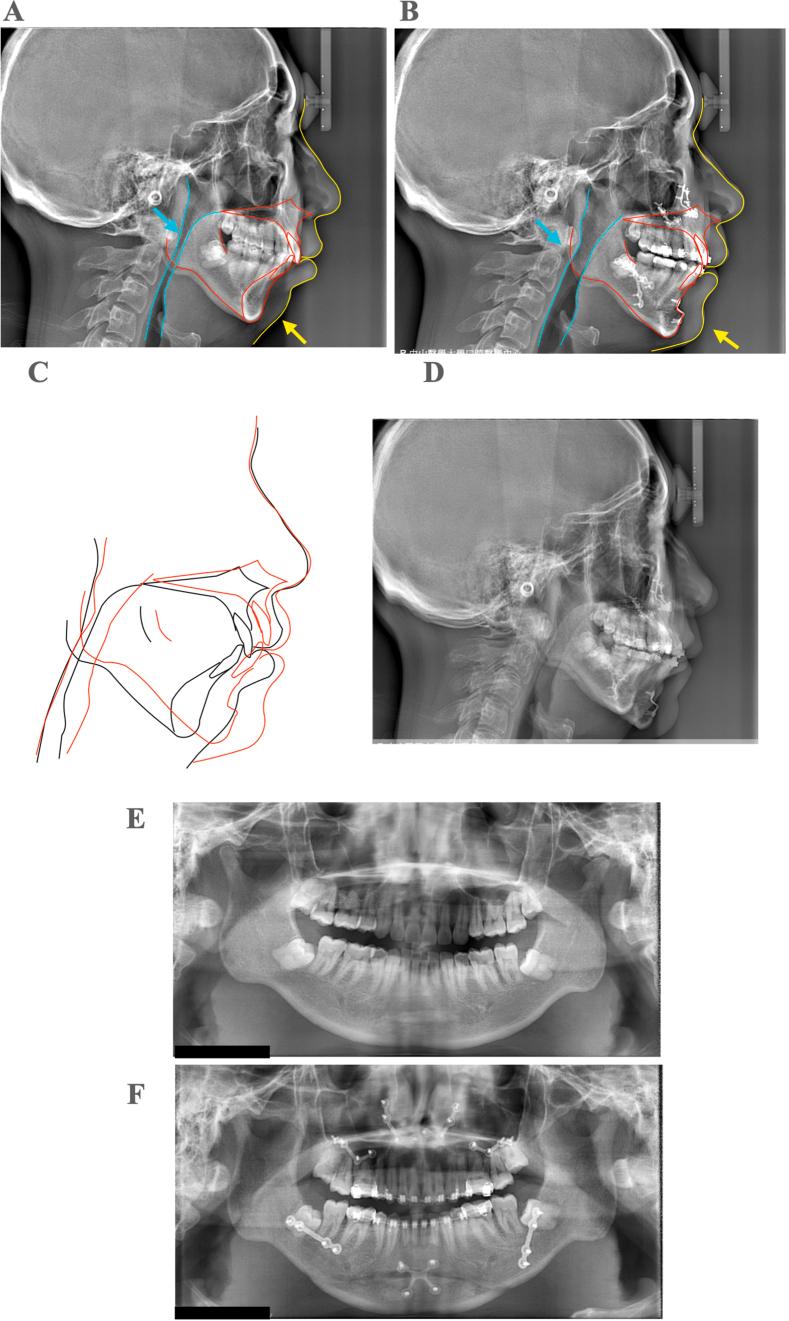

Maxillomandibular advancement surgery can alleviate mental health issues associated with obstructive sleep apnea syndrome.

J Dent Sci. 2024 Apr;19(2):1263-1265. doi: 10.1016/j.jds.2023.10.031. Epub 2023 Nov 22.